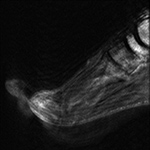

Figure 15 Figure 16 Figure 17 Figure 18A

MRI motion artifact MRI pulsation artifact Wraparound artifact Truncation artifact

Motion Artifact. Degraded image quality of sagittal T1-weighted fat-saturated post-contrast MR image of the foot due to patient motion.